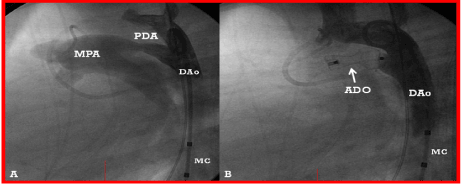

Although the results of the occlusion of PDAs [4,16,17,25,26], ASDs [27-33], VSDs [22] and APW [5] with the buttoned device appear satisfactory and are truly comparable to the other devices [34-37], following the completion of FDA-sponsored clinical trials, the inventor of the device decided not to seek pre-market approval (PMA) and, therefore, the device is no longer available for clinical use [38]. Consequently, the author uses Gianturco coils to occlude very small and small PDAs (Figures 7 and 8) and Amplatzer Duct Occluder (Figure 9), Amplatzer Duct Occluder II (Figure 10), and Amplatzer Vascular Plug (Figure 11) for moderate to large PDAs.

Figure 9. A. A selected cine frame from an aortic arch angiogram in lateral view, demonstrating a moderate-sized patent ductus arteriosus (PDA) opacifying the main pulmonary artery (MPA). B. Following the implantation of an Amplatzer duct occluder (ADO), no residual shunt is seen. Also, there is no descending aortic (DAo) obstruction. MC, Marker pigtail catheter.